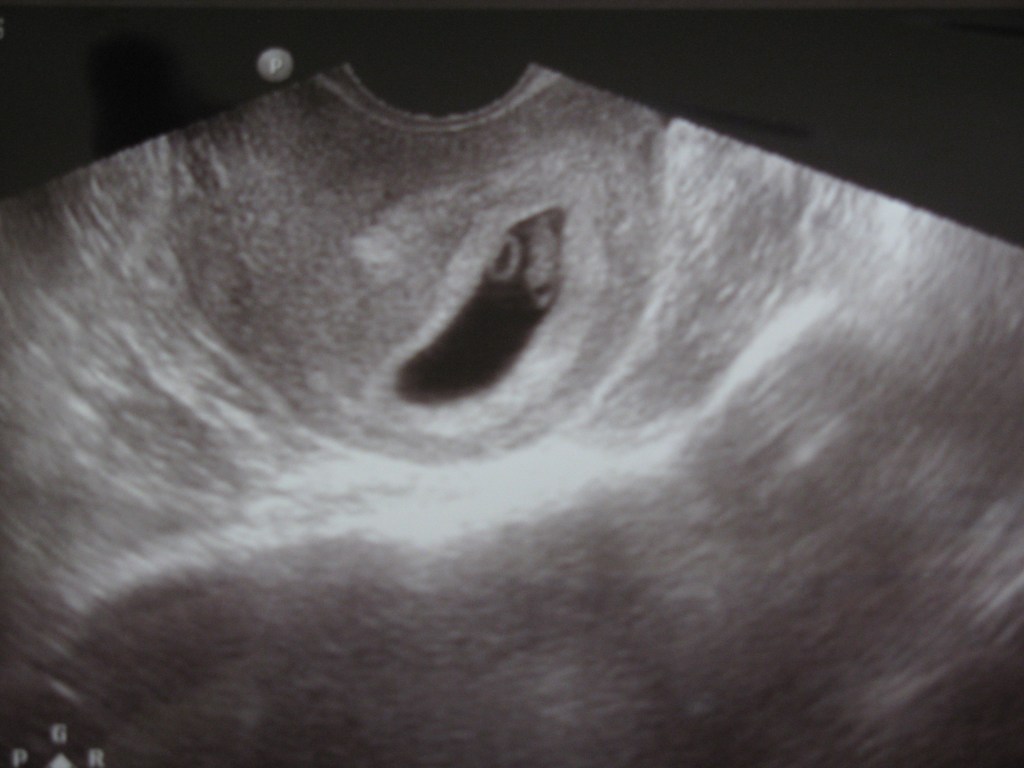

Pictures of the first glimpse of our second cute baby: